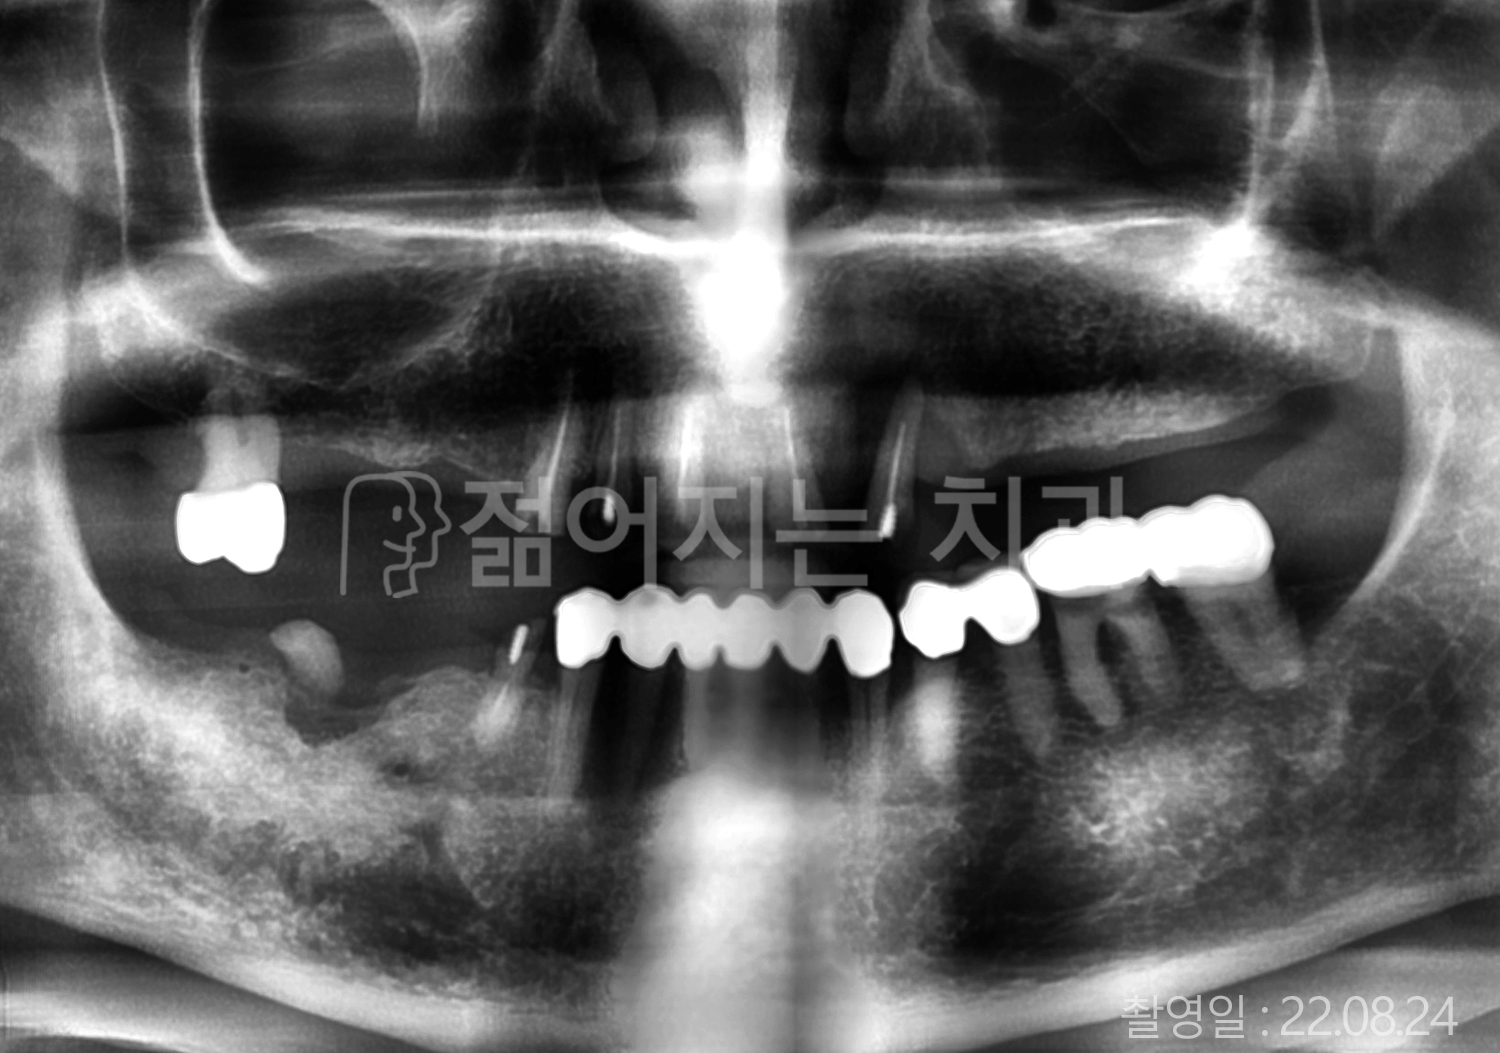

• 70대 고혈압, 당뇨 전체치아 10개 이상 임플란트

• 50대 고혈압, 당뇨 전체치아 10개 이상 임플란트

• 60대 고혈압, 당뇨 전체치아 10개 이상 임플란트

• 50대 전체치아 10개 이상 임플란트

• 70대 당뇨 전체치아 10개 이상 임플란트

• 80대 전체치아 10개 이상 임플란트

• 40대 전체치아 10개 이상 임플란트

• 60대 고협압, 고지혈증 전체치아 10개 이상 임플란트

• 60대 전체치아 10개 이상 임플란트